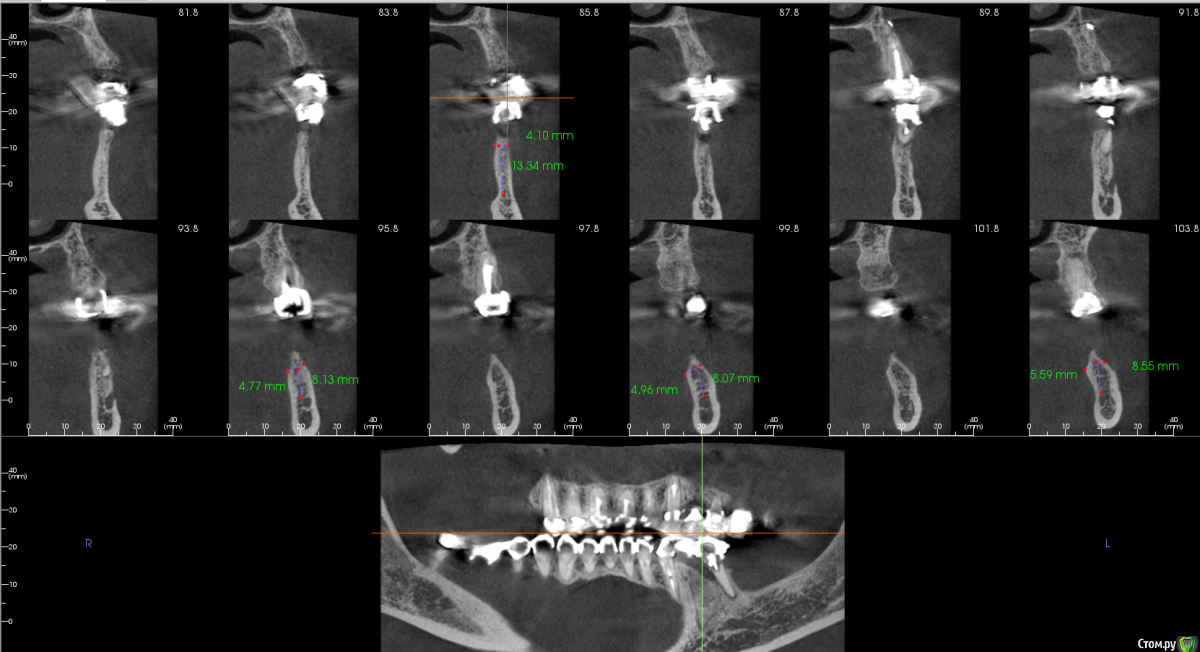

kamranchick Опубликовано 31 октября, 2018 Автор Поделиться Опубликовано 31 октября, 2018 Шаг 2 мм... Ссылка на комментарий

Bier Опубликовано 2 ноября, 2018 Поделиться Опубликовано 2 ноября, 2018 я честно говоря не понял в каком месте среза сколько кости. Где-то кости достаточно для установки имплантата без пластики, где-то нет. Ссылка на комментарий

kamranchick Опубликовано 3 ноября, 2018 Автор Поделиться Опубликовано 3 ноября, 2018 вот еще такие реформаты Ссылка на комментарий

Bier Опубликовано 3 ноября, 2018 Поделиться Опубликовано 3 ноября, 2018 блин, Камранчик, я вообще не понимаю в какую зону ты хочешь ставить и как твою нарезку прикрепить к панораме, которая ниже. Никакой системы координат нет.Короче там, где гребень 4.7 - можно крутить и не делать пластик. Ссылка на комментарий